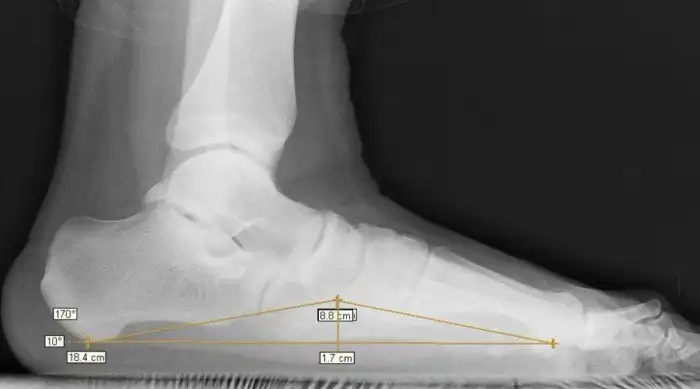

Что это такое

В здоровой стопе природное соединение подвижных костей составляет два свода. Они выполняют амортизирующую функцию. Врожденные пороки или внешние факторы могут привести к тому, что стопа становится плоской и соприкасается с поверхностью — соотвественно, амортизационная функция перекладывается на другие части тела, которые не предназначены для таких нагрузок. С этого и начинаются настоящие проблемы для всего организма.